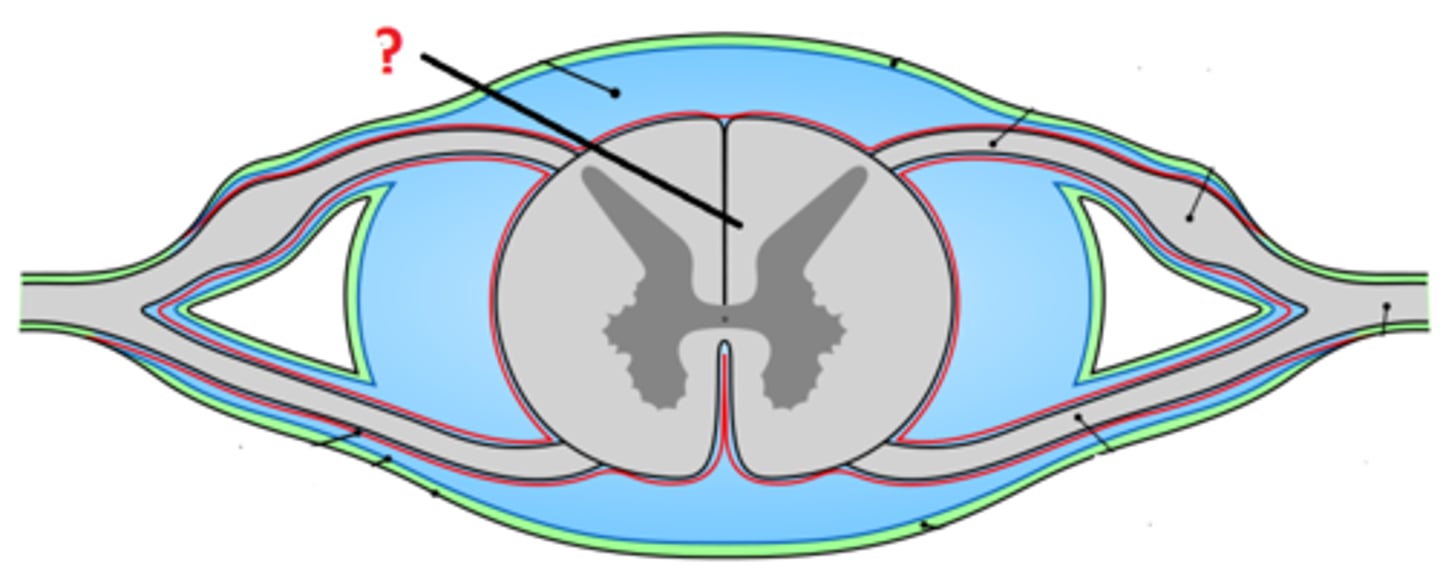

arachnoid mater

dura mater

denticulate ligament

pia mater

subdural space

epidural space

subarachnoid space